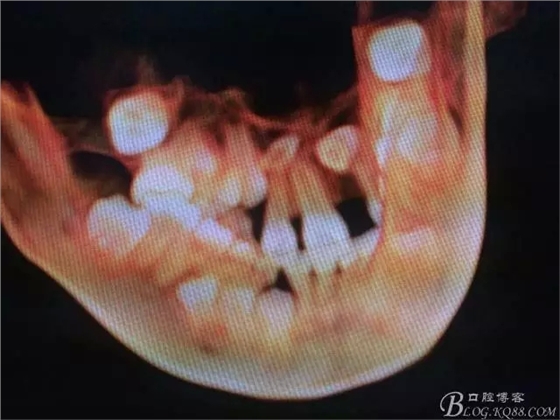

圖2.術(shù)前的CBCT的三維影像重建:多生牙的位置

圖3.右上11的三維影像位置。